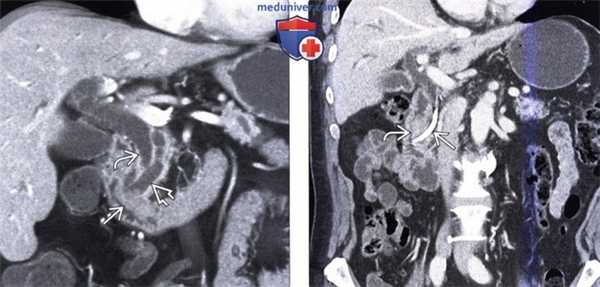

(Слева) На корональной КТ с контрастным усилением (объемный рендеринг) определяется симптом «двойного протока» на фоне обструкции общего желчного и печеночного протоков, обусловленной полиповидным объемным образованием (рак) ампулы фатерова сосочка.

(Справа) На корональной КТ с контрастным усилением визуализируется дискретное объемное образование вокруг ампулы фатеровы сосочка, в которой находится билиарный стент. Рак ампулы сложно отличить от периампулярного рака двенадцатиперстной кишки методами визуализации, но, тем не менее, лечение в обоих случаях одинаково (операция Уиппла).